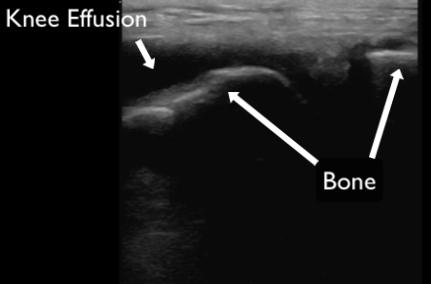

There are many joints that can be easily visualized with ultrasound and the technique varies based on the anatomical location and specific clinical question being addressed. Effusions appear as anechoic collections within and around joint spaces (Figure 17). POCUS is useful not only for identifying effusions, but for planning and performing joint injections or arthrocentesis. Tendon pathology is often identified near joint spaces at points of insertion. Finally, dislocation can be identified by appreciating abnormal articulation or gapping of the joint space (Figure 18). Evaluating the contralateral joint is helpful as a comparison of normal anatomy.

Figure 16. An anechoic collection of fluid identified as a joint effusion in a patient’s knee.